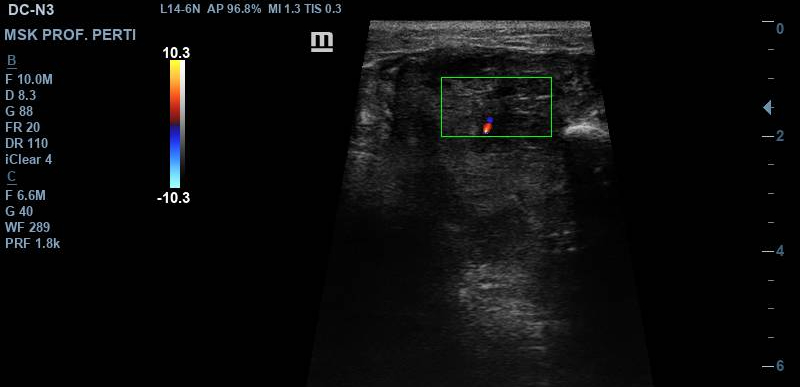

La ecografía muestra una lesión sólida hipoecoica, heterogénea y de contornos irregulares, situada entre la musculatura gemelar lateral y la musculatura peronea, con tamaño aproximado de 2,6–3,2 cm. Presenta áreas anecoicas compatibles con degeneración quística, pequeños focos hiperecogénicos sugestivos de calcificaciones y engrosamiento fascial con pérdida de la arquitectura normal. El estudio Doppler identifica vascularización interna arterial y venosa. Los hallazgos son compatibles con lesión mesenquimal profunda y potencialmente agresiva.